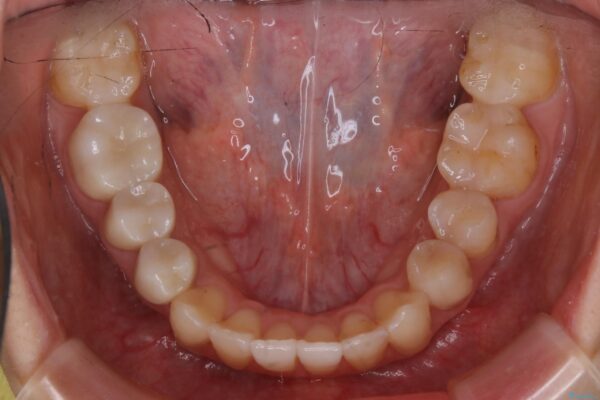

治療前

20代 女性 非抜歯で歯列をコンパクトに20代 女性 非抜歯で歯列をコンパクトに20代 女性 非抜歯で歯列をコンパクトに